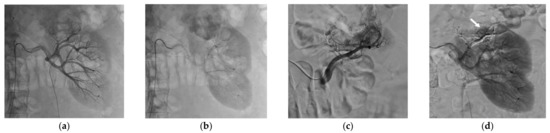

Table 4 reports the features of the PCA procedures. Complete ablation was obtained for all patients and no immediate complications were visible on the control unenhanced CT-scan performed at the end of the procedure. Five patients required hydrodissection prior to ablation. No patient reported more than moderate pain after PCA. No ice-ball cracking occurred. Figure 3 and Figure 4 show examples of PCA of renal cell carcinoma after SAE.

Figure 4.

CT-guided percutaneous cryoablation procedure of a renal cell carcinoma of the left kidney performed after selective arterial embolization using NBCA/Lipiodol® mixture. (a) Enhanced CT-scan for trajectory planification showing a complete devascularization of the tumor with lipiodol uptake. Note that the left colon is really close to the kidney. (b) CT acquisition showing the hydrodissection technique with needle placement for injection of dextrose solution to repel the colon and protect it. (c) Unenhanced control CT-scan post-ablation showing the optimal coverage of the tumor without any immediate complication.